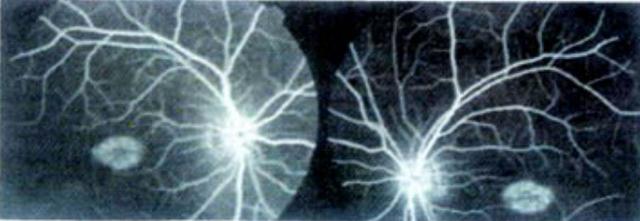

弱视的危害远远大于近视,因为单纯近视的儿童,看远模糊,看近清楚,视觉细胞和神经还能受到外界物象的刺激而不会衰退,而弱视则不同,由于视觉细胞和神经长期受不到外界物象的准确刺激而衰退,如果不及时防治,视力便会永久低下。因此弱视对于患者来说,将一辈子影响生活、学习和工作,在他们眼里,立体视觉模糊,因而不能准确地判断物体的方位和远近。